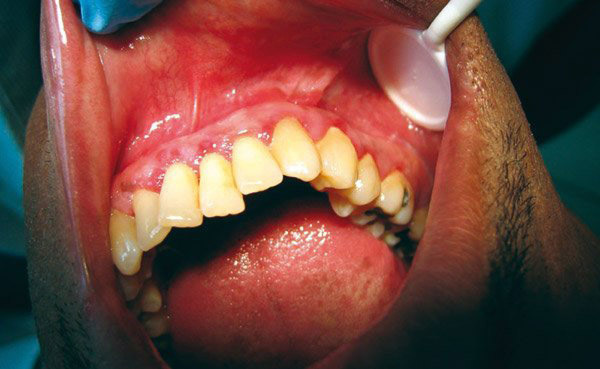

Guy Princ, La Revue du Praticien Gingivite due à la plaque dentaire. La gencive au collet des dents (du tartre dentaire) est érythémateuse et légèrement hypertrophique.